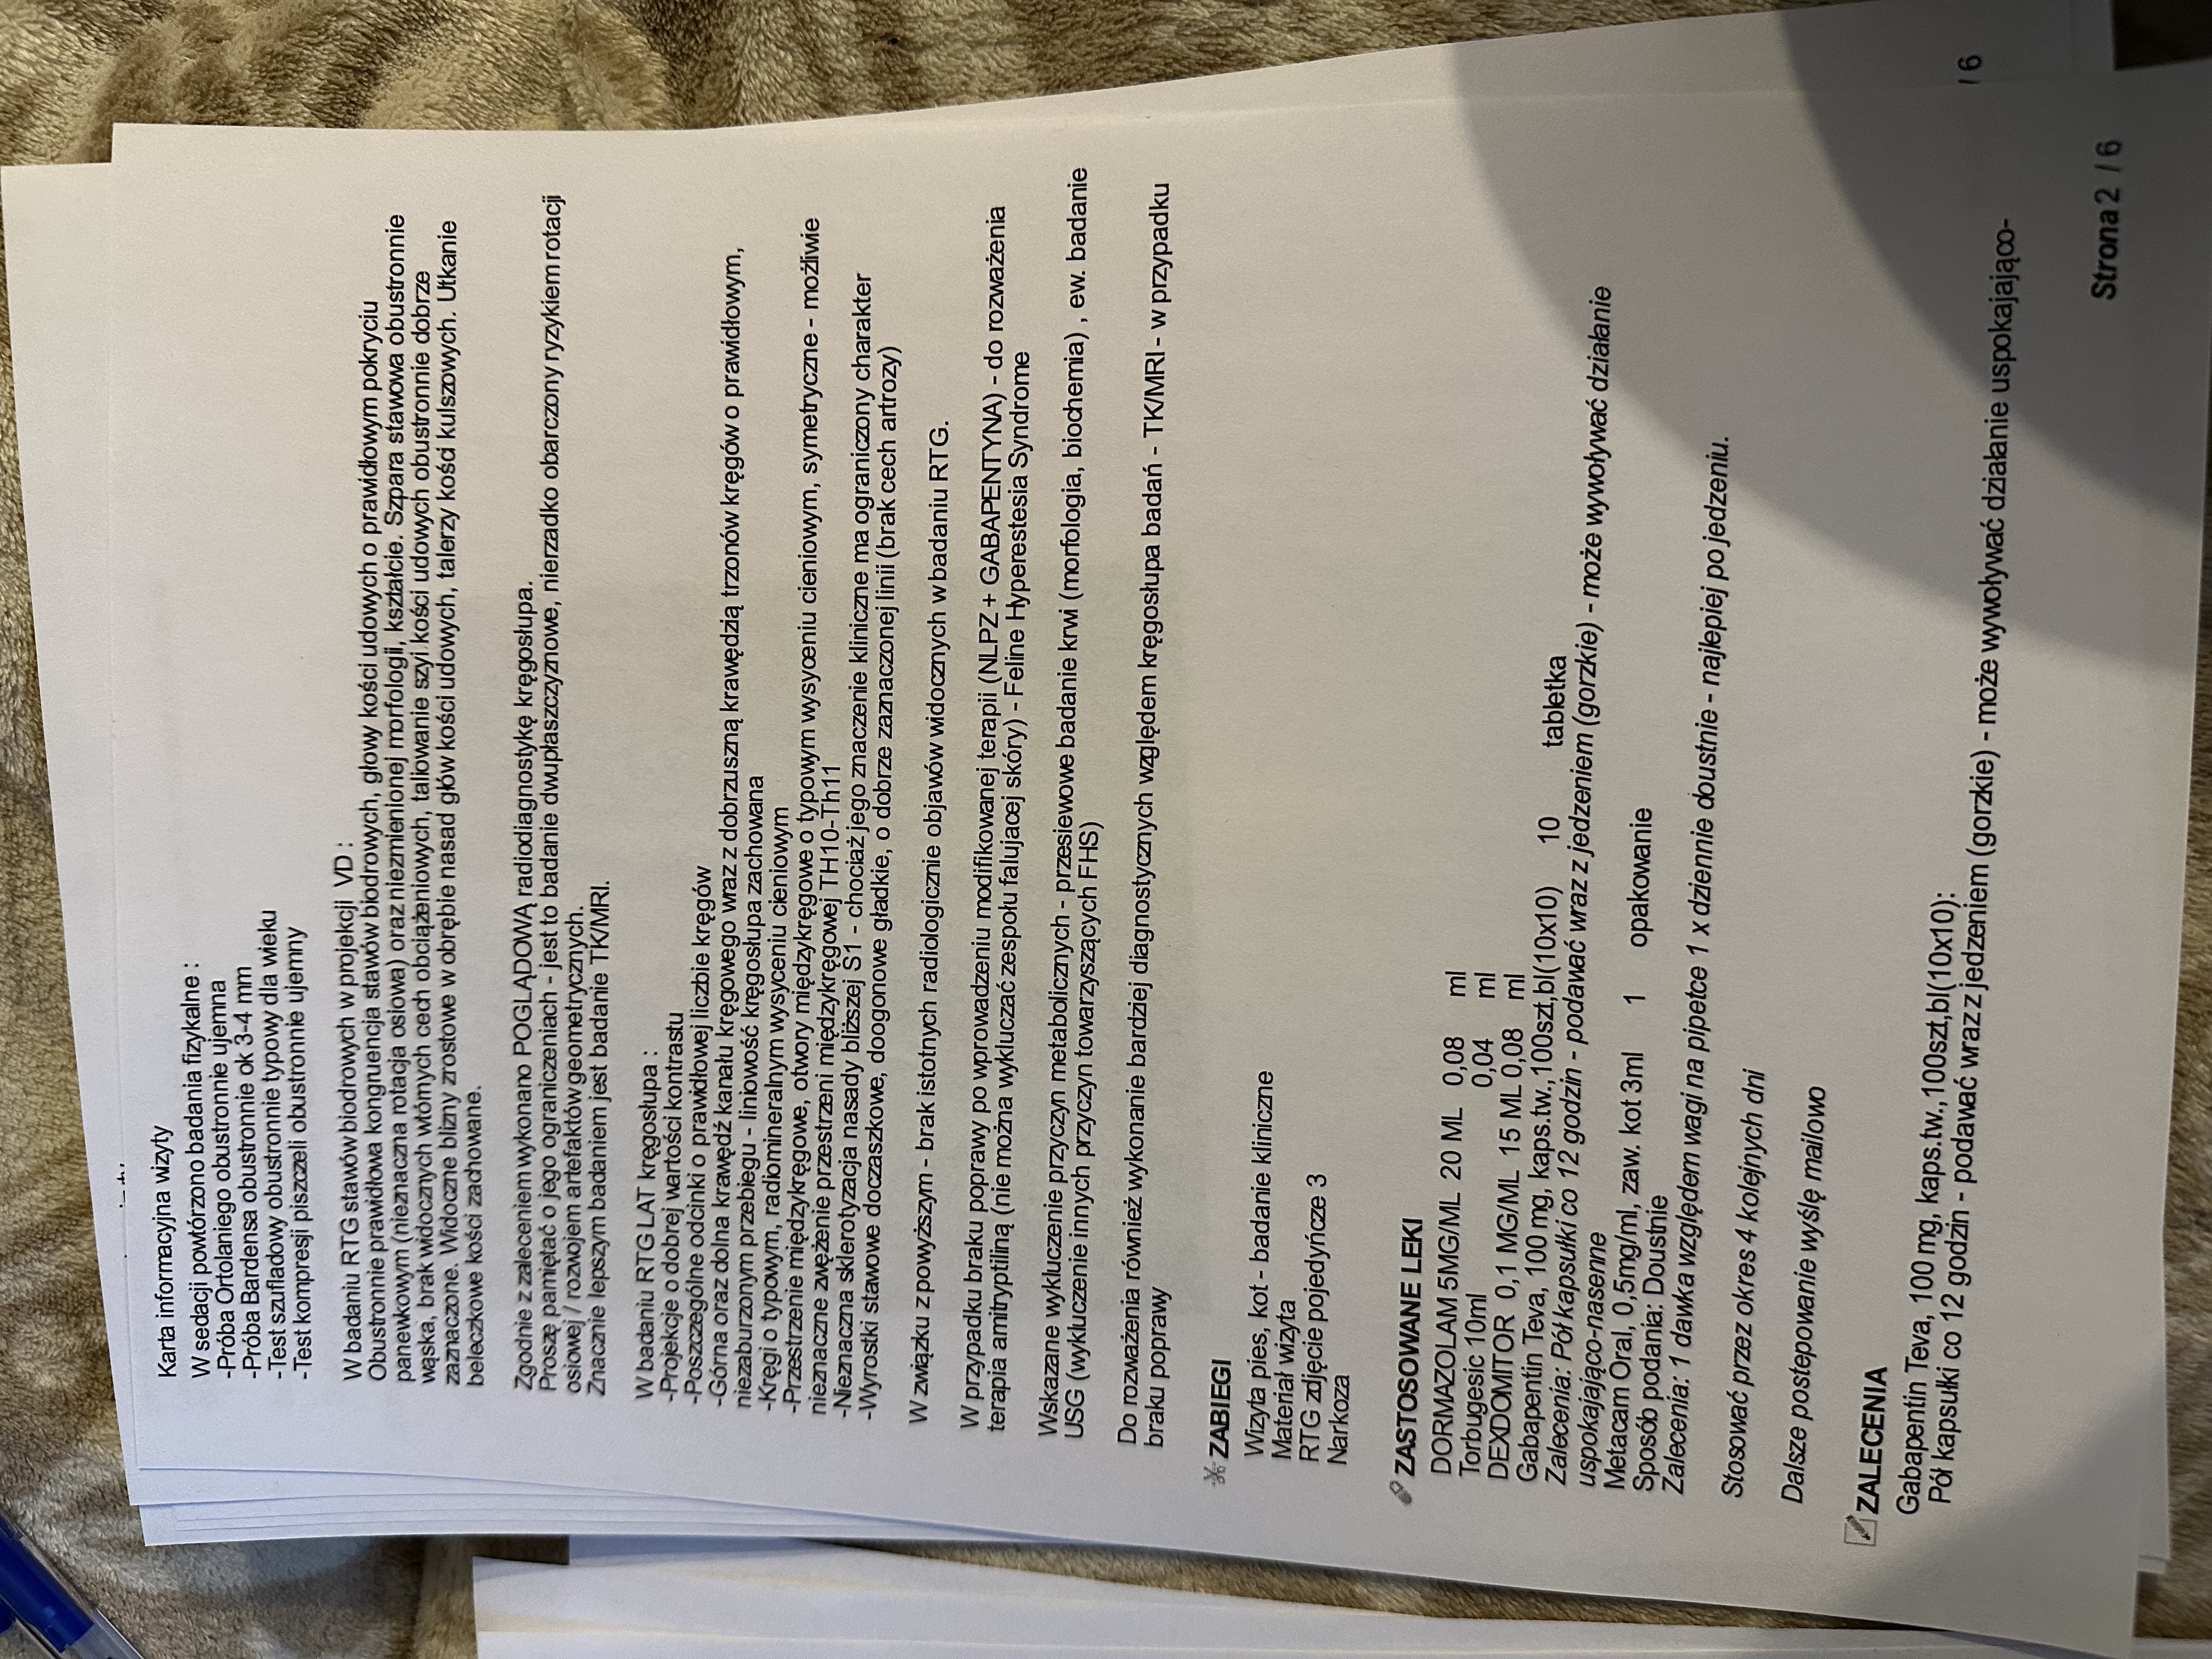

Kolejna konsultacja miała miejsce w innej klinice, gdzie lekarze nadal podejrzewali problemy ortopedyczne, dlatego przeszedł szczegółowe badania, w tym RTG kręgosłupa i bioder i konsultacje specjalistyczną. Wdrożono leczenie Gabapentyną oraz Metacamem, aby zmniejszyć ból i uspokoić kota. Zalecono dalszą obserwację oraz ewentualne kolejne badania, jeśli objawy nie ustąpią.

Kot wymagał dalszej diagnostyki – możliwe kolejne badania ortopedyczne (TK/MRI) oraz USG i biochemię z morfologią.

Badania ortopedyczne oraz biochemia wraz z morfologią nie wykazały poważnych zmian (lekarza poinformował, aby nie decydować się na badanie TK/MRI, ponieważ podłoże problemu leży gdzieś indziej; a z USG się wstrzymać).

Pojawiło się podejrzenie Feline Hyperesthesia Syndrome (FHS) – zaburzenia neurologicznego, które może powodować nadwrażliwość skóry, niekontrolowane reakcje bólowe oraz zmiany w zachowaniu, a także zostało przeprowadzone badanie kliniczne i nie wykluczono problemów dermatologicznych w związku z agresywnym wydrapywaniem futerka (alergia, pasożyty). Zalecono obserwację i sprawdzenie reakcji na leki sterydowe.

Lekarz wprowadził leczenie objawowe, aby sprawdzić, czy Fudżi dobrze na nie zareaguje: Amitryptylina – lek przeciwdepresyjny i przeciwbólowy, stosowany przy zaburzeniach Pnrednicorton (steryd) – silny lek przeciwzapalny, mający zmniejszyć stan zapalny i świąd.